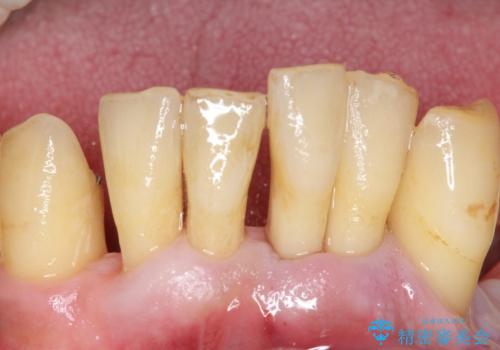

精査したところ、全顎的な重度の歯周病により下顎前歯に激しい動揺を認めました。

できるだけ自分の歯を残したいという患者様の強いご希望により、禁煙指導後再生療法(骨を増やす手術))を行いました。

骨吸収と動揺が著しい前歯1本(左下1)のみ抜歯しております。